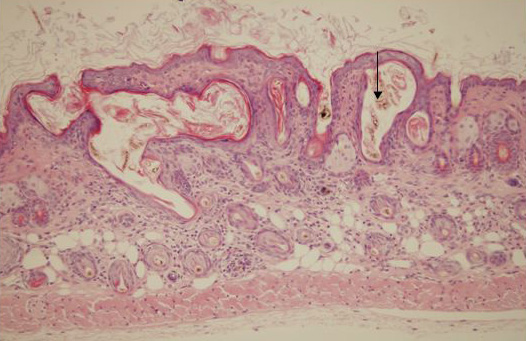

Caption Ass1fold/Ass1fold mice have displastic hair follicles as show here (note arrow). The hair folicle does produce a normal hair fiber.

Ass1fold argininosuccinate synthetase 1; follicular dystrophy

Ass1fold/Ass1fold B6Ei.P-Ass1fold/GrsrJ